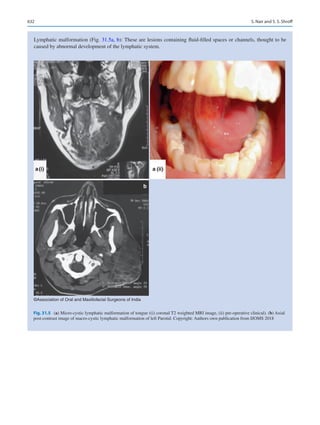

Surgical robots are also constantly evolving incorporating

precision haptics and AI. Robotic arms can already perform

tasks independent of a surgeon yielding it. Imperfections and

errors that a surgeon may cause in an operation are avoided

in robotic surgery by consistent movements, angles, and

access that can only be achieved by that robot. Imagine a

robotic arm that can be programed to remove a mesioangular

impacted mandibular third molar? The robot surgeon can